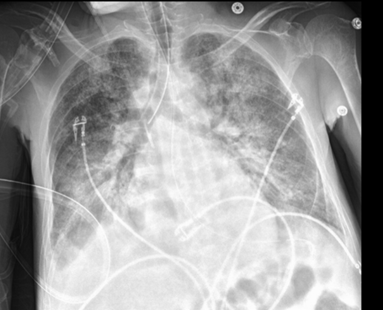

This could happen if the ET tube is advanced too far.

What is a right mainstem intubation?

This could occur if a mainstem intubation is not realized for a while.

What is an atelectatic L Lung?